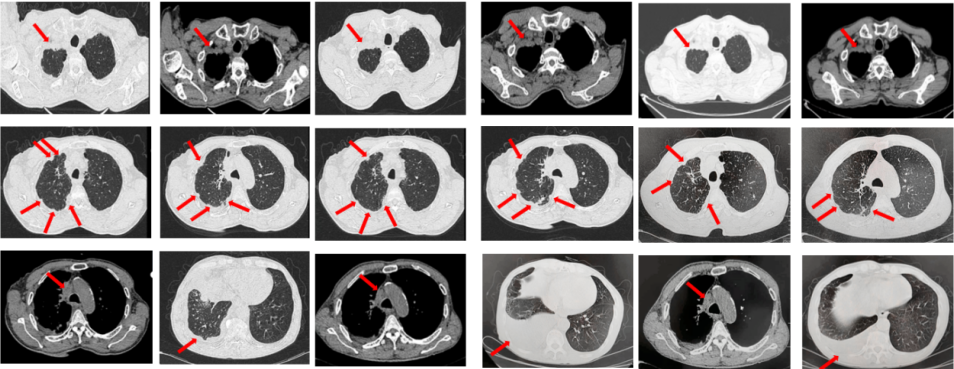

如图7所示,2021年7月复查评效PD。重新行右肺穿刺取得病理,提示腺癌。NGS组织基因检测:MET基因扩增(变异倍数)4.0倍。改行赛沃替尼联合奥希替尼治疗。治疗10日后突发一过性寒战伴低血压,不除外药物相关,对症治疗后好转。复查评效达PR,因患者无法耐受药物不良反应,改行奥希替尼联合克唑替尼治疗至今,定期复查,最佳评效PR,末次评效SD(2024年7月)。

图7:A.奥希替尼治疗后病情进展,右肺内病灶较前再次增大,同时右肺内新发转移灶;B.出现MET扩增后,奥希替尼联合MET-TKI治疗后肺内病灶较前明显缩小;C.当前方案治疗持续有效。

67岁女性患者,无既往病史。2019年10月患者因右侧季肋部不适行肺CT提示右肺中叶改变,双肺结节,右侧胸腔积液。行右侧胸腔穿刺引流,送检胸腔积液,液基薄层结果提示肺腺癌。确诊为右肺中叶恶性肿瘤cT2bN1M1a IVA期。基因检测(胸腔积液):EGFR L858R突变。建议患者口服奥希替尼,患者拒绝。2019年11月始口服埃克替尼,定期复查,最佳评效PR(图5)。

图5:A.第2例患者的基线影像资料,由上至下依次为右肺肿物、双肺转移灶及右侧胸腔积液;B.EGFR-TKI一线治疗后最佳复查评效,肺内病灶较前缩小,胸腔积液较前明显吸收。

2020年11月复查评效PD。复测基因检测(血检):T790M阳性,改行奥希替尼治疗,期间评效均为SD(图6)。

图6:A.埃克替尼靶向治疗后病情进展,肺内病灶较前增大,右肺近胸膜处新发转移灶;B.更换三代EGFR-TKI治疗后复查多处病灶未见明显变化。